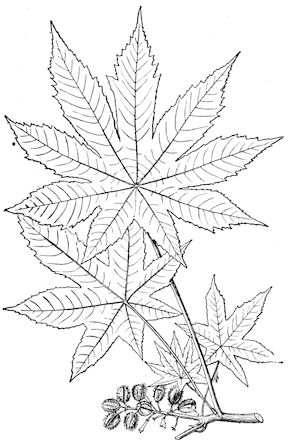

Fig. 1.—Rachitis in a young goat.